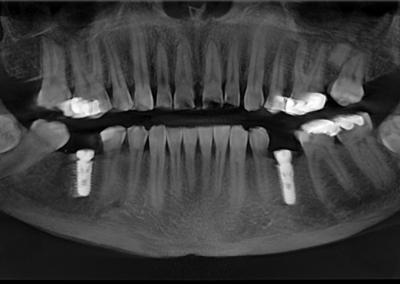

We start with a comprehensive full mouth examination, digital X-rays, a dental 3D(CBCT) scan and Trios5 Scan. The scanned images provide high-resolution images in a three dimensional plane. We use these images and scans for precise treatment planning.

CBCT 3D Scan

Using the 3D images in special planning software, the Dentist maps out the exact position and angle of insertion of each implant. They take care to place implants where they will be stable and in the best position to support the replacement teeth. They will also plan out any bone grafting (if needed) to ensure the implants have strong bone support.